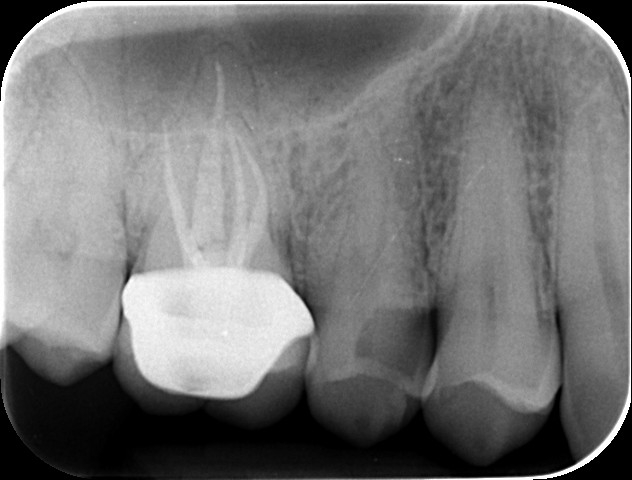

Case 6 – Periodontics

Crown lengthening Surgery on a premolar